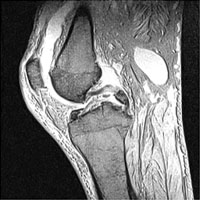

Tibial Fracture (PCL Avulsion)

The anterior cruciate ligament attaches on or adjacent to the medial tibial spine of the intercondylar eminence while the posterior cruciate ligament attaches to the posterior surface of the tibia. Fractures of the medial tubercle (spine) therefore indicate that the ACL has been likely be torn from the tibia.

- Click on the image for a larger versionASagittal MRI. This gradient echo sequence image shows avulsion of a portion of the posterior tibia by the PCL.